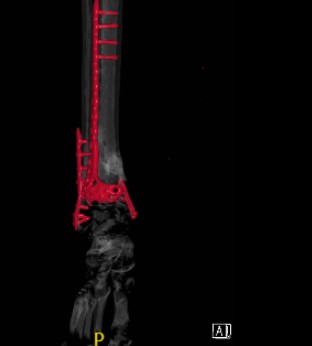

Comminuted fracture of the tibia which has been transfixed with surgical pins as well as can be determined in the position of the surgical instruments appears satisfactory. The plaster splint is in place.

Status post ORIF with plate and screws in the distal fibula and tibia with 2 screws in the medial malleolus. A portion of the fracture line is still evident in the tibia.

Radiographs and CT scan confirmed healing fractures with a congruent mortise, but hardware impingement on dorsiflexion and eversion.

Status post ORIF with plate and screws in the distal fibula and distal tibia with healed fracture of the distal shaft of the tibia with mild deformity with anatomic alignment maintained.Healed fracture of the distal fibula without residual deformity.